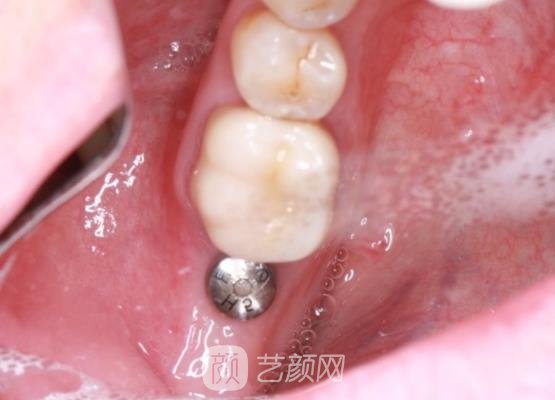

今天我到医院进行牙冠安装的时候,医生的手法还是一如既往的轻柔,所以并没有给我带来不适感。虽然安装上牙冠之后,感觉口腔有一些异物感存在,不过这都是正常现象,我能够接受。